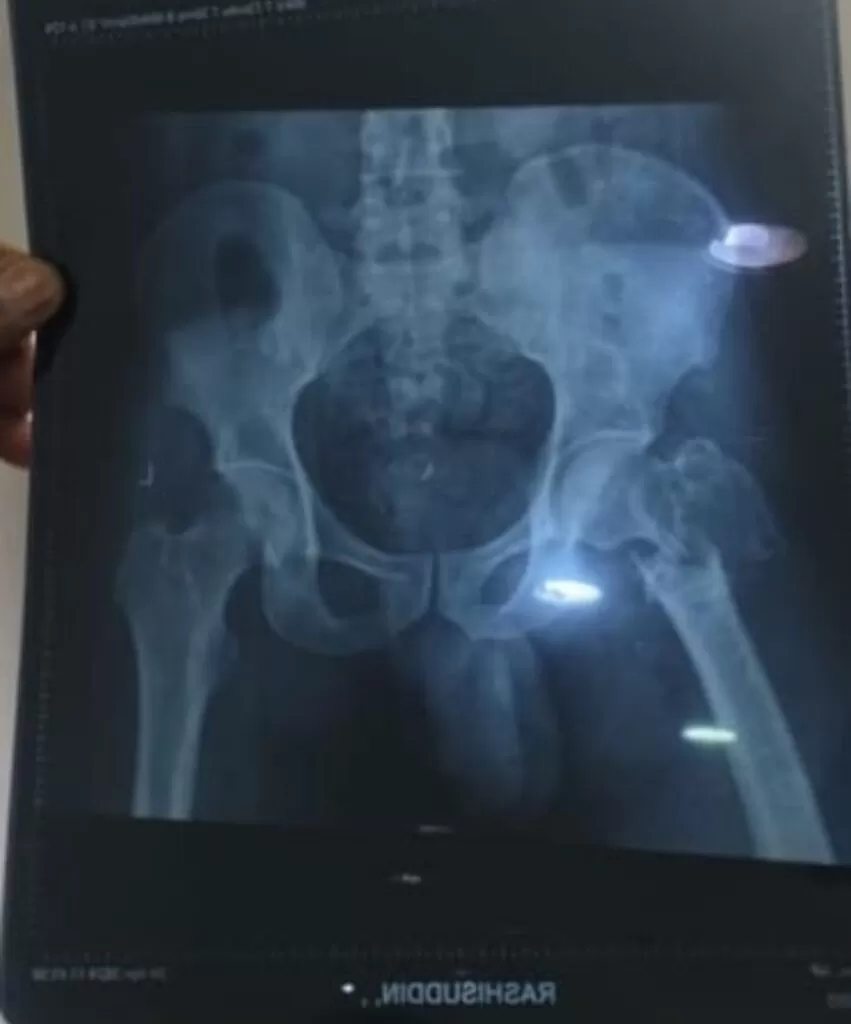

Mr. Rahisuddin

Name: Mr. Rahisuddin

Date of Operation: 04 May 2024

Age: 25 Years